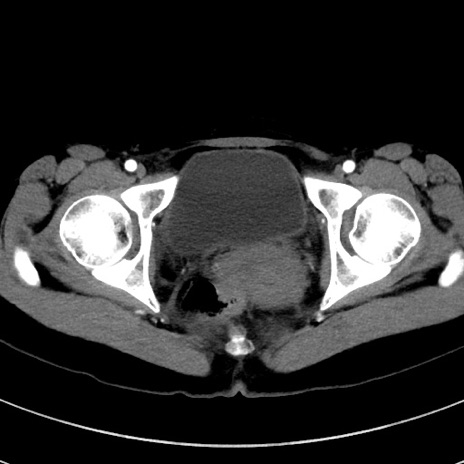

症例17(横断像)

【症例】20歳代女性

【主訴】嘔吐、下腹部痛

【現病歴】昨日夕食後に嘔吐し下腹部痛が出現。本日になっても嘔吐持続し改善しないため来院。

【身体所見】意識清明、BT 37.2℃、BP 108/67mmHg、腹部:平坦、やや硬、下腹部正中から右にかけて圧痛あり、反跳痛軽度あり、tapping pain(+)。

【データ】WBC 13600、CRP 14.94